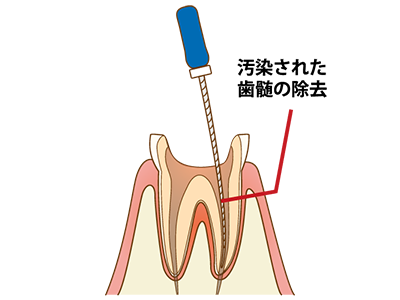

2 歯の中にある神経をファイルと呼ばれる細い器具で取り除きます(抜髄)

3 既に根管治療がしてある歯の場合には、古くなって汚れた樹脂製のお薬を取り除きます(再根管治療)

4 根管の中を徹底的に清掃・消毒し、バクテリアや腐敗した歯髄組織を取り除いてきれいにします